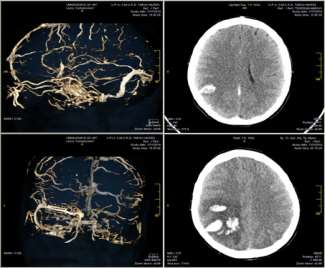

Hình ảnh 1: Chảy máu não trên phim chụp CLVT sọ não của người bệnh tại Bệnh viện Bạch Mai.